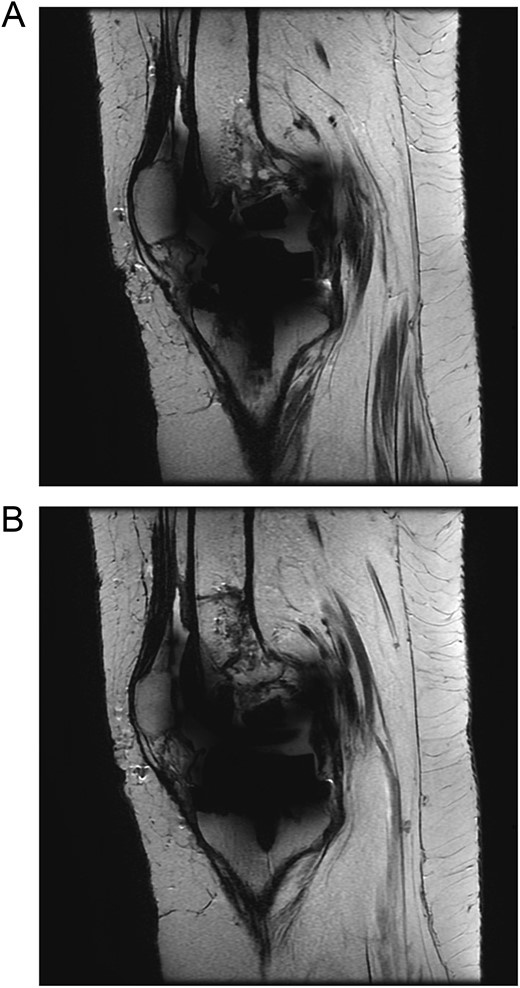

The patient was admitted for investigation. Routine radiographic imaging was unremarkable. Magnetic resonance imaging (MRI) and computed tomography scans were conducted and revealed no abnormalities (Figs 3 and 4). Afterward, the patient was examined under anesthesia, where a stable joint was noted with full knee ROM. The only remarkable finding was the clicking sound with flexion. The impression was that there was polyethylene wear due to the significant weight gain, and the decision was made to discharge the patient with instructions to lose weight and to re-admit electively for TKA revision and possible polyethylene exchange if there was no improvement.

Computed tomography (CT scan) of bilateral knees showing no abnormality.

Although polyethylene fracture is diagnosed clinically, some imaging modalities are being used to aid in diagnosis. One case reported that taking a lateral radiograph of the knee while in extension may show a posterior displacement of the femur, which may confirm the diagnosis of post-fracture [9]. In addition, MRI may be used to diagnose polyethylene fractures. Although several cases in the literature have done this, most cases with positive MRI results have shown fractured polyethylene intraoperatively [10]. In our case, the MRI possibly did not show the post-facture as the post was not displaced, making it difficult to be seen.